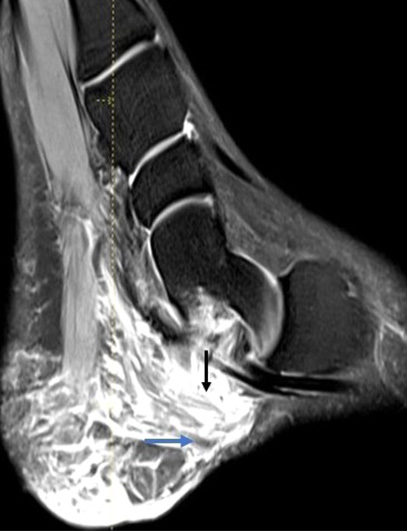

Plantar fibrolipomatous hamartoma in a patient with neurofibromatosis type 1.

Singh S., Kowe P., Sawatkar G., Meshram N.

pp. 238-40